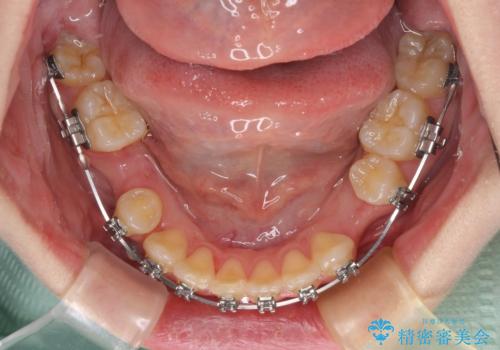

- 矯正装置

- メタルブラケット

- 上下の八重歯を気にして来院された患者様です。

非抜歯矯正で歯列を整えると、治療後に口元が今よりも突出する可能性が高かったため、上下左右の小臼歯4本を抜歯し、ワイヤー装置にて矯正治療を行うこととしました。

右上の八重歯の影響で、右側は上顎歯列が前方位の咬み合わせとなってしまっていたため、上顎は第一小臼歯を、下顎は第二小臼歯を抜歯することで咬み合わせや上下正中を調整することとしました。